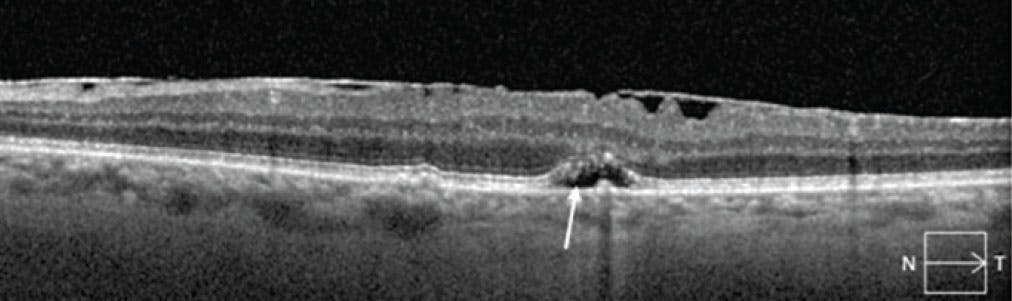

One study in the literature investigated nonexudative SRF in GA and observed a high percentage of progression to GA in areas of SRF overlying drusen and drusenoid pigment epithelial detachments.14 Our findings corroborate that these areas of nonexudative SRF likely represent a degenerative space beneath the retina, rather than an exudative fluid process, and are risk factors for progression to GA (Figure 1).13 SHRM/AVLs in the setting of dry AMD have more recently been hypothesized to represent an accumulation of various breakdown materials due to significant RPE stress and dysfunction or to act as a physical barrier for nutrient exchange, accelerating photoreceptor degeneration and GA progression (Figure 2).15,16

<p>Figure 2. The arrow points to a hyperreflective area representative of SHRM/AVLs that later progressed to GA.</p>

Figure 2. The arrow points to a hyperreflective area representative of SHRM/AVLs that later progressed to GA.